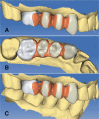

Figure 2 A, B, C

Teeth preparation. Supra-gingival (tooth N. 13) and juxta-gingival (tooth N. 16) margin placement. A) Lateral view. B) Occlusal view. C) A higher magnification of the preparation (tooth N. 13).